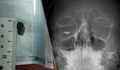

Лекари от Александровска болница спасиха зрението на дете след тежка травма